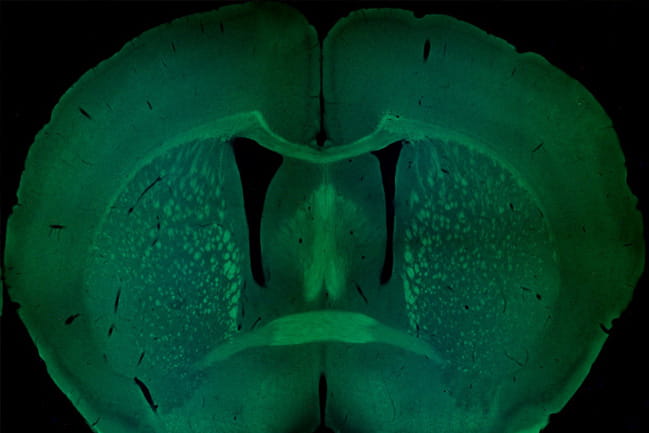

Coronal section of a mouse brain, with several major axonal tracts stained in green.

Coronal section of a mouse brain, with several major axonal tracts stained green.